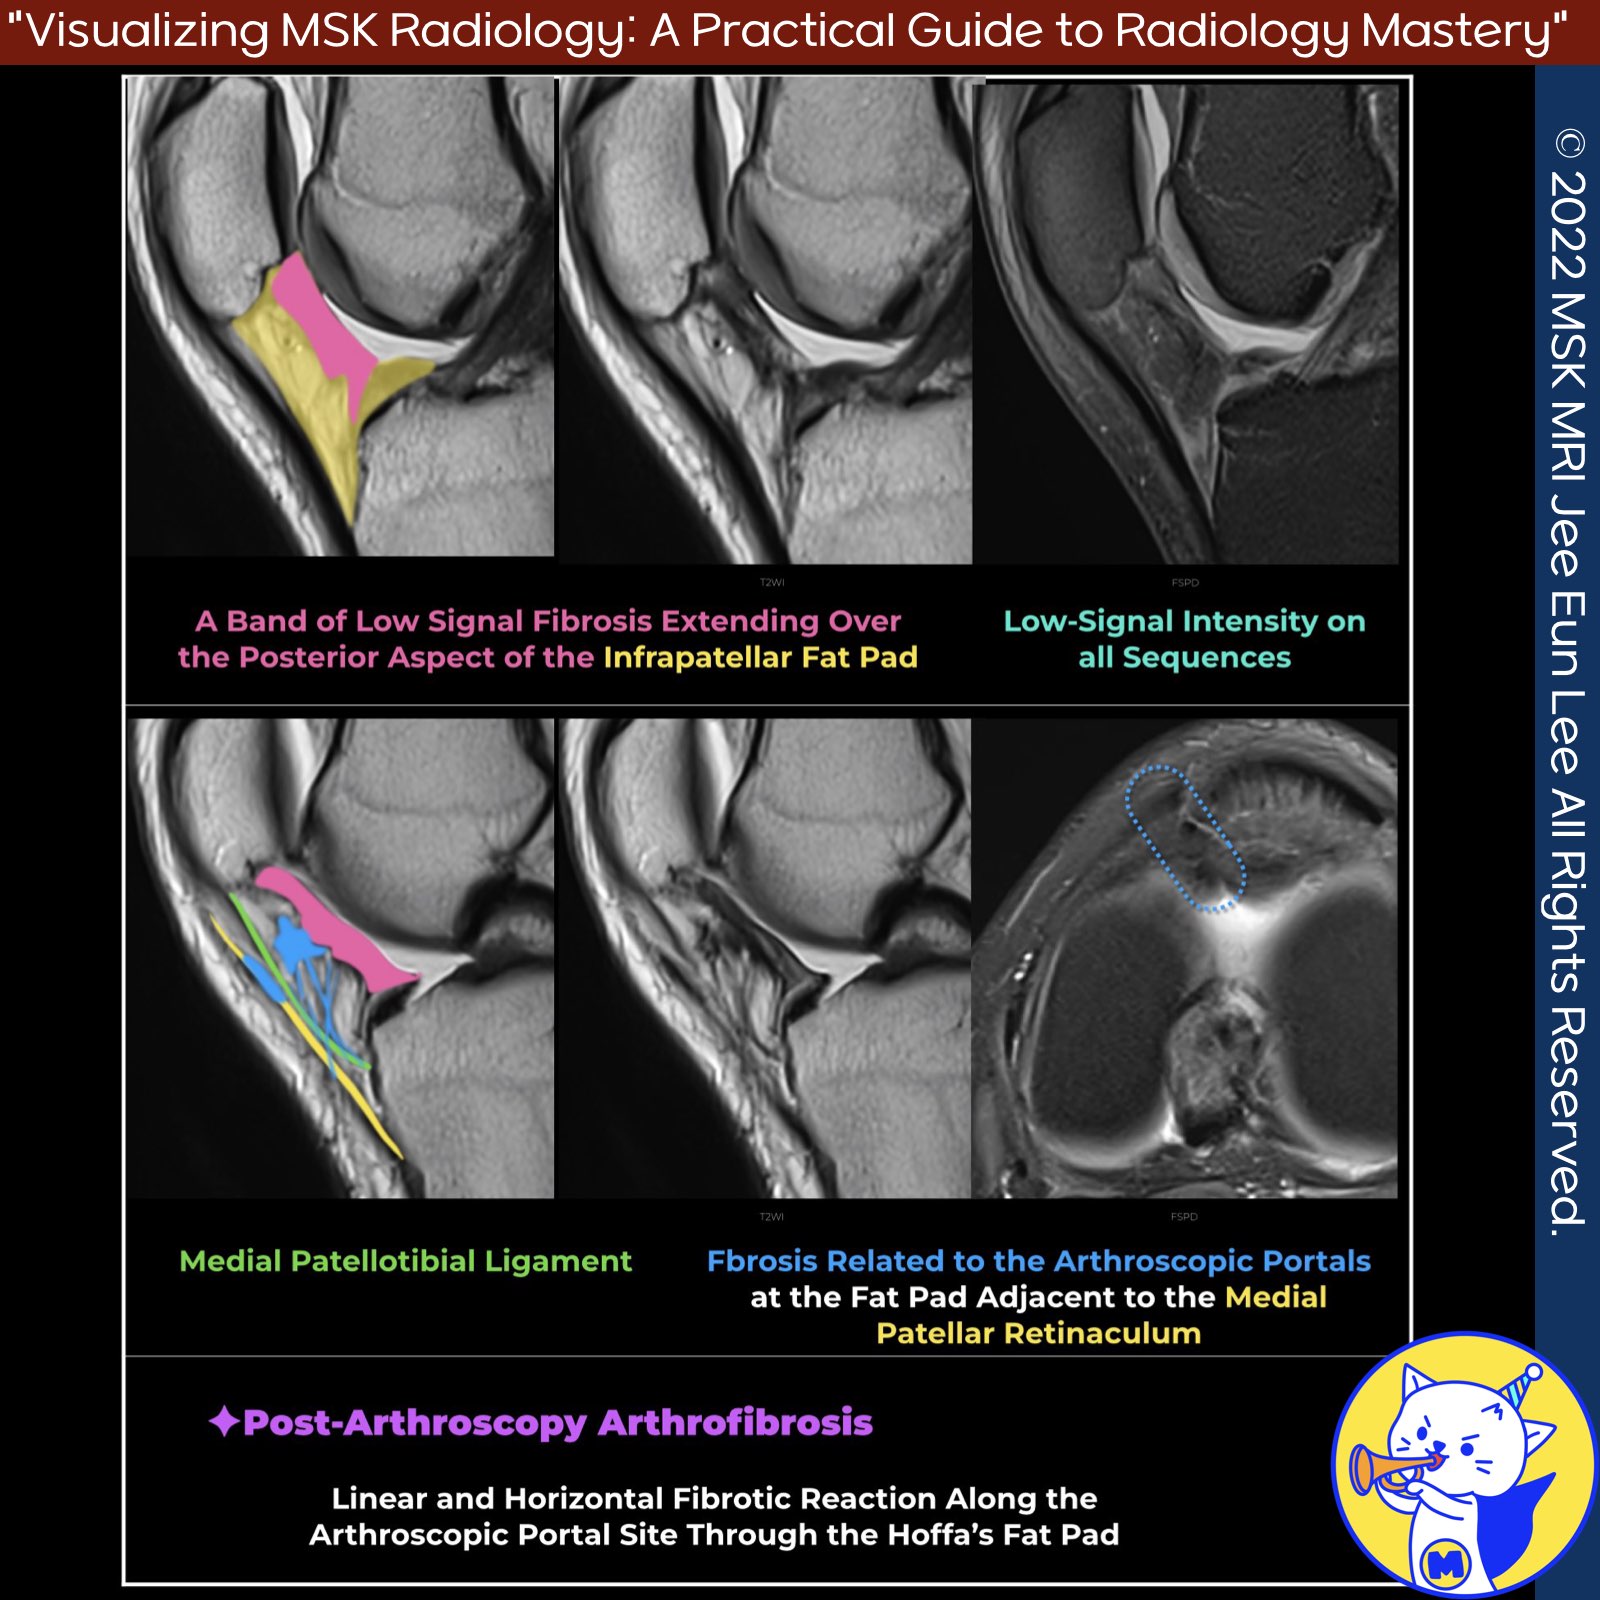

📌Postsurgical Changes at the Fat Pad

- Postsurgical changes at the fat pad are significant considerations in postoperative assessments, particularly after arthroscopic procedures.

- These changes primarily include fibrosis and tissue metaplasia, which can affect the patient’s recovery and functional outcomes.

✅ Fibrosis Post-Arthroscopy

- Postarthroscopy fibrosis is often subtle and may present as thin regions of linear fibrosis related to the arthroscopic portals.

- These fibrotic changes typically occur at the superficial fat pad adjacent to the medial patellar retinaculum.

- The initial post-arthroscopy appearance is usually characterized by a linear and horizontal fibrotic reaction along the arthroscopic portal site through the Hoffa fat pad.

✅ Arthrofibrosis

- Arthrofibrosis is a common complication following ACL reconstruction.

- Patients may experience stiffness or restricted extension, which can mimic graft impingement symptoms.

- This condition can manifest as a cyclops lesion, a fibrotic nodular mass in the anterior intercondylar notch .

- Additionally, arthrofibrosis can surround the graft or appear as low-signal scarring within the Hoffa fat pad.